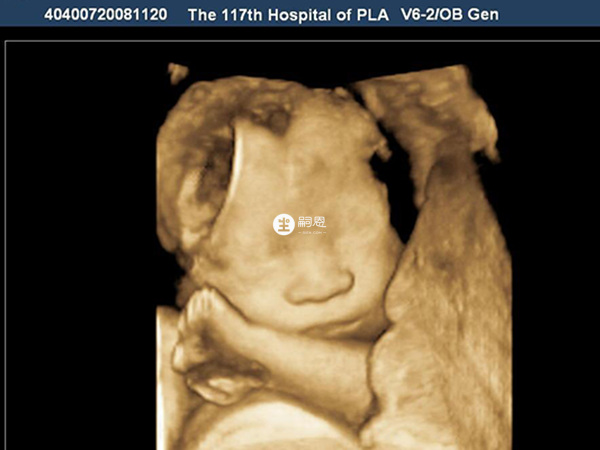

絨毛穿刺和nt檢查的區別在於檢查時間不同、出報告時間不同、採取方式不同等。最直觀的就是絨毛穿刺屬於是確診檢查,而nt則屬於是篩查,在準確率上面絨毛穿刺會更高。做絨毛穿刺和nt檢查的區別是絨毛穿刺是穿刺時用穿刺針穿過孕婦的腹壁刺入宮腔吸出少許絨毛進行檢查,而nt檢查是又稱為頸後透明帶掃描,是評估胎兒是否患有唐氏綜合症的一種方法,檢測的是胎兒頸部面板厚度,如果nt檢查說有問題的話,醫生會建議再做一個絨毛穿刺。

絨毛穿刺和nt檢查都是孕期必備的孕檢專案,很多時候如果nt檢查沒有過的話會再讓檢查絨毛穿刺,很多的孕婦不知道這兩個有何區別,那麼絨毛穿刺和nt檢查的區別是什麼呢?具體的區別如下。